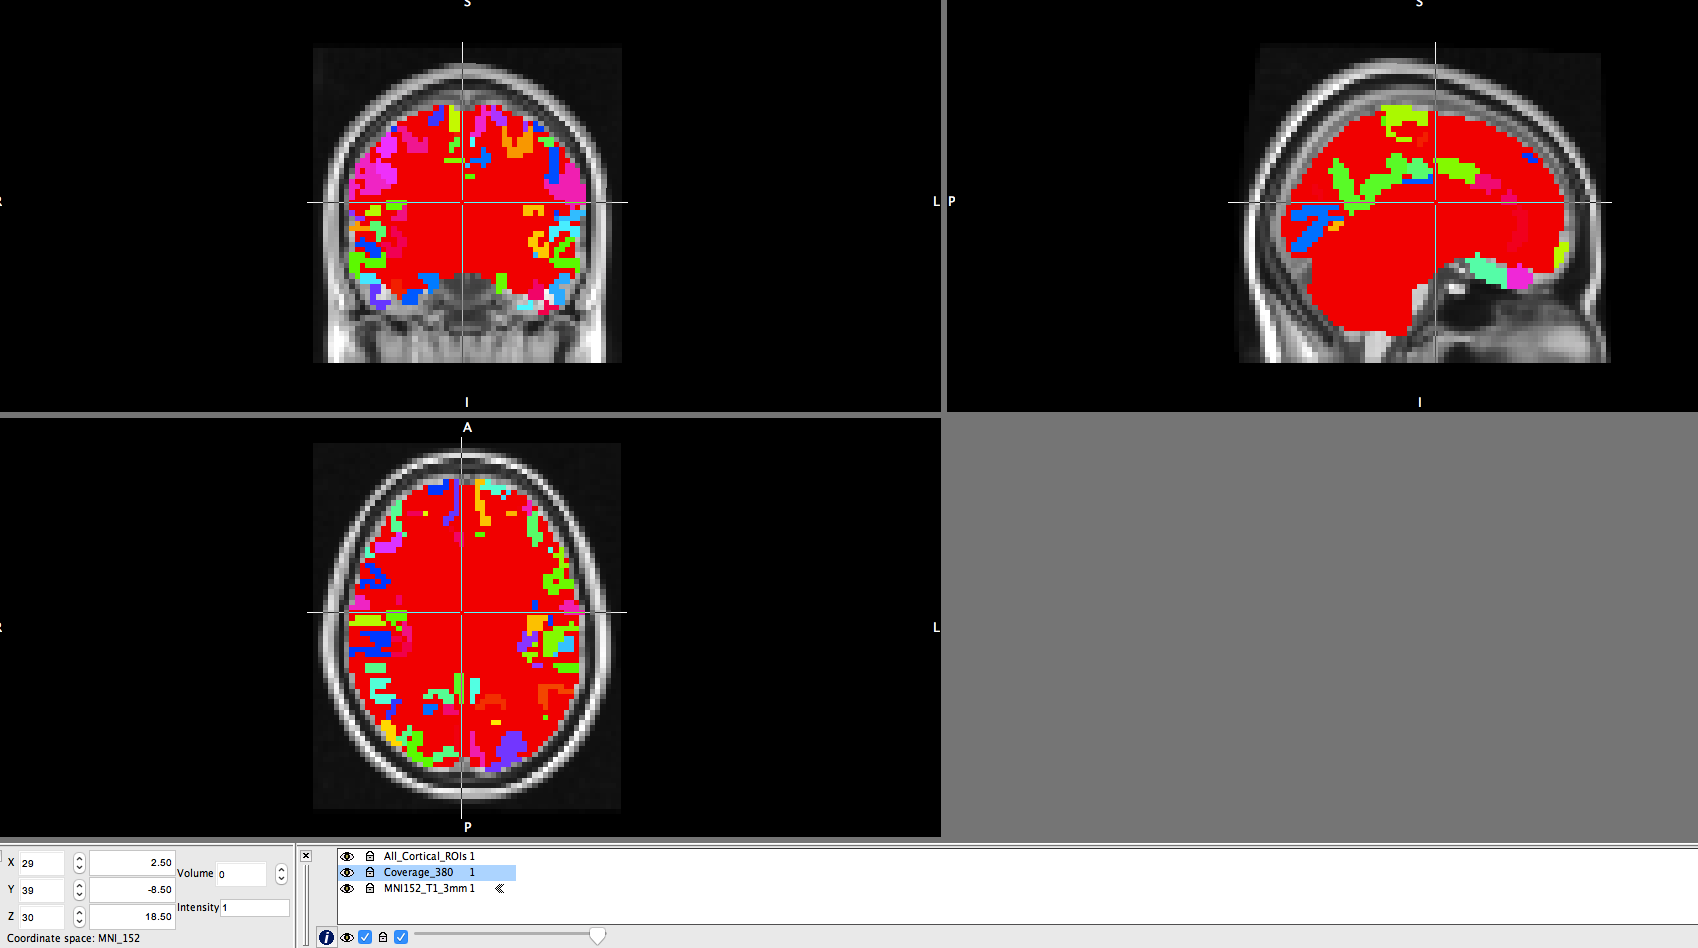

I have created the a mask for an fmri analysis.

I have loaded the mask and ROIs in to the FSL.

Few ROIs are outside the mask.

How can I find the ROIs that are outside the mask?